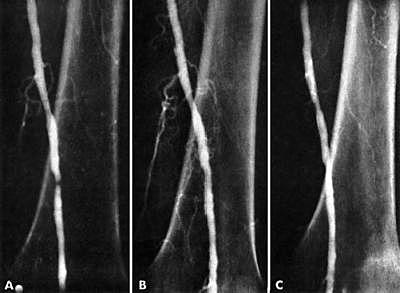

• Restoring Blood Flow

Restoring Blood Flow

82 year old woman, Laura Shaw, was an inpatient at University of Oregon Hospital with an ischemic left foot. After refusing numerous physician recommendations of an amputation, Dr. Dotter and his trainee successfully performed percutaneous transluminal angioplasty (PTA) of the superficial femoral artery (SFA) using a balloon attached onto a catheter. The patient was able to walk out of the hospital weeks later.